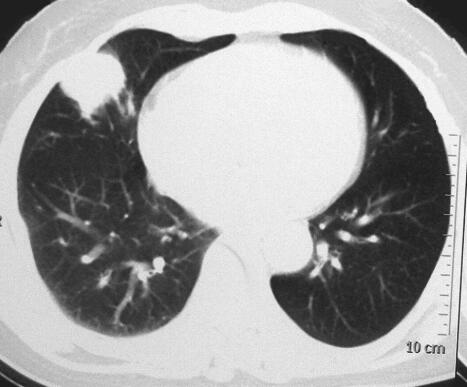

入院后查体:生命体征平稳,呼吸平稳,浅表淋巴结未扪及肿大。胸廓外形正常,双肺触觉语颤正常,双肺呼吸音清,未闻及干湿性啰音。辅助检查提示:血常规、肝肾功能、生化及心电图未见异常。胸部增强CT提示:右肺中叶团块影(图1)。纤维支气管镜刷片提示:鳞状上皮化生伴重度异型增生。入院后给予雾化、化痰等对症治疗,于2013年2月3日行右肺中叶切除术及纵隔淋巴结清扫术。术中发现胸内未见明显粘连积液,肺表面可见少量炭末沉着,肺裂发育好,占位位于右肺中叶,约3cm×2.5cm×2cm大小,累及脏层胸膜。见第2、3、4、7、9、10和11组淋巴结肿大。经过仔细止血及生理盐水胸腔冲洗后,逐层关闭患者的胸腔。手术切除的肺组织体积为10cm×5cm×3cm,支气管全长0.7cm,直径1cm。支气管黏膜较光滑,距支气管断端2.2cm紧邻胸膜下肺组织内可见一肿物,大小为3cm×2cm×1.5cm,肿物切面灰白灰褐,实性,质中,

图1 右肺中叶团块影